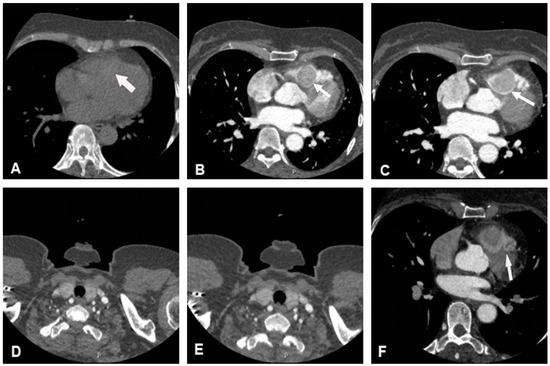

The cine cardiac magnetic resonance (CMR) images showed a hypointense mass with regular contours, which adhered to the interventricular septum and protruded into the right ventricular cavity. The signal intensity of the mass was high on T2-weighted images, without any signal decrease on the fat suppression sequence. However, pericardial or pleural effusion was not observed. CMR rest perfusion sequences demonstrated a rapid signal increase in the mass following an augmentation in the left ventricular blood pool signal, which implied that the mass was perfused by the aorta, and then a rapid decrease in signal intensity on early gadolinium enhancement (Figure 3). Moreover, myocardial delayed gadolinium enhancement was considerably lower than the blood pool signal at the same level.

Figure 3.

Cardiac magnetic resonance imaging. (A) Cine images of magnetic resonance imaging showed a hypointense mass. (B) The signal intensity of the mass was high on T2-weighted images. (C,D) The mass showed a rapid enhancement on CMR rest perfusion. (E) The signal intensity of the mass decreased rapidly on early gadolinium enhancement. (F) Myocardial delayed gadolinium enhancement was significantly lower than the blood pool signal at the same level. White arrows indicate the location of the mass in each image.